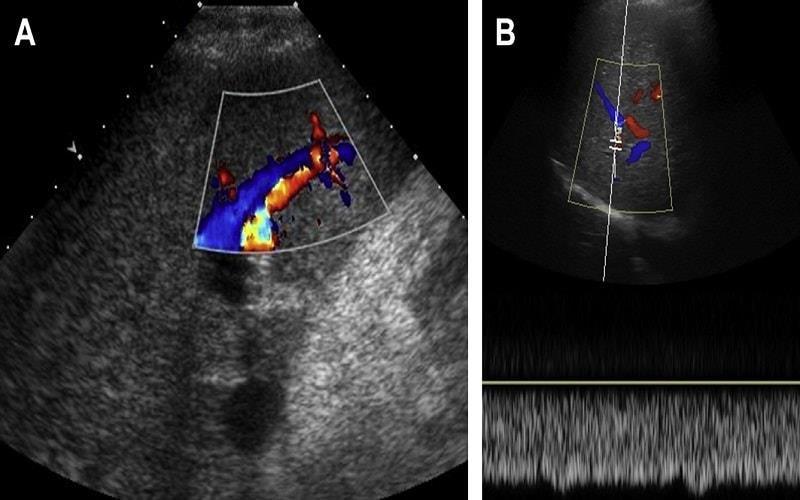

Siêu âm gan là phương pháp hàng đầu trong chẩn đoán hình ảnh ở bệnh nhân ung thư gan, được các cơ sở y tế lớn áp dụng nhiều bởi có chi phí thấp, thực

hiện đơn giản, không gây tác dụng phụ và cho tỷ lệ chẩn đoán chính xác cao (có thể phát hiện khối u gan kích thước trên 1cm).

Siêu âm hỗ trợ bác sĩ lên phác đồ điều trị ung thư gan như cắt gan, tiêm diệt u

qua da,… Tuy nhiên, siêu âm ung thư gan cho biết vị trí và kích thước khối u mà không cho biết bản chất khối u.